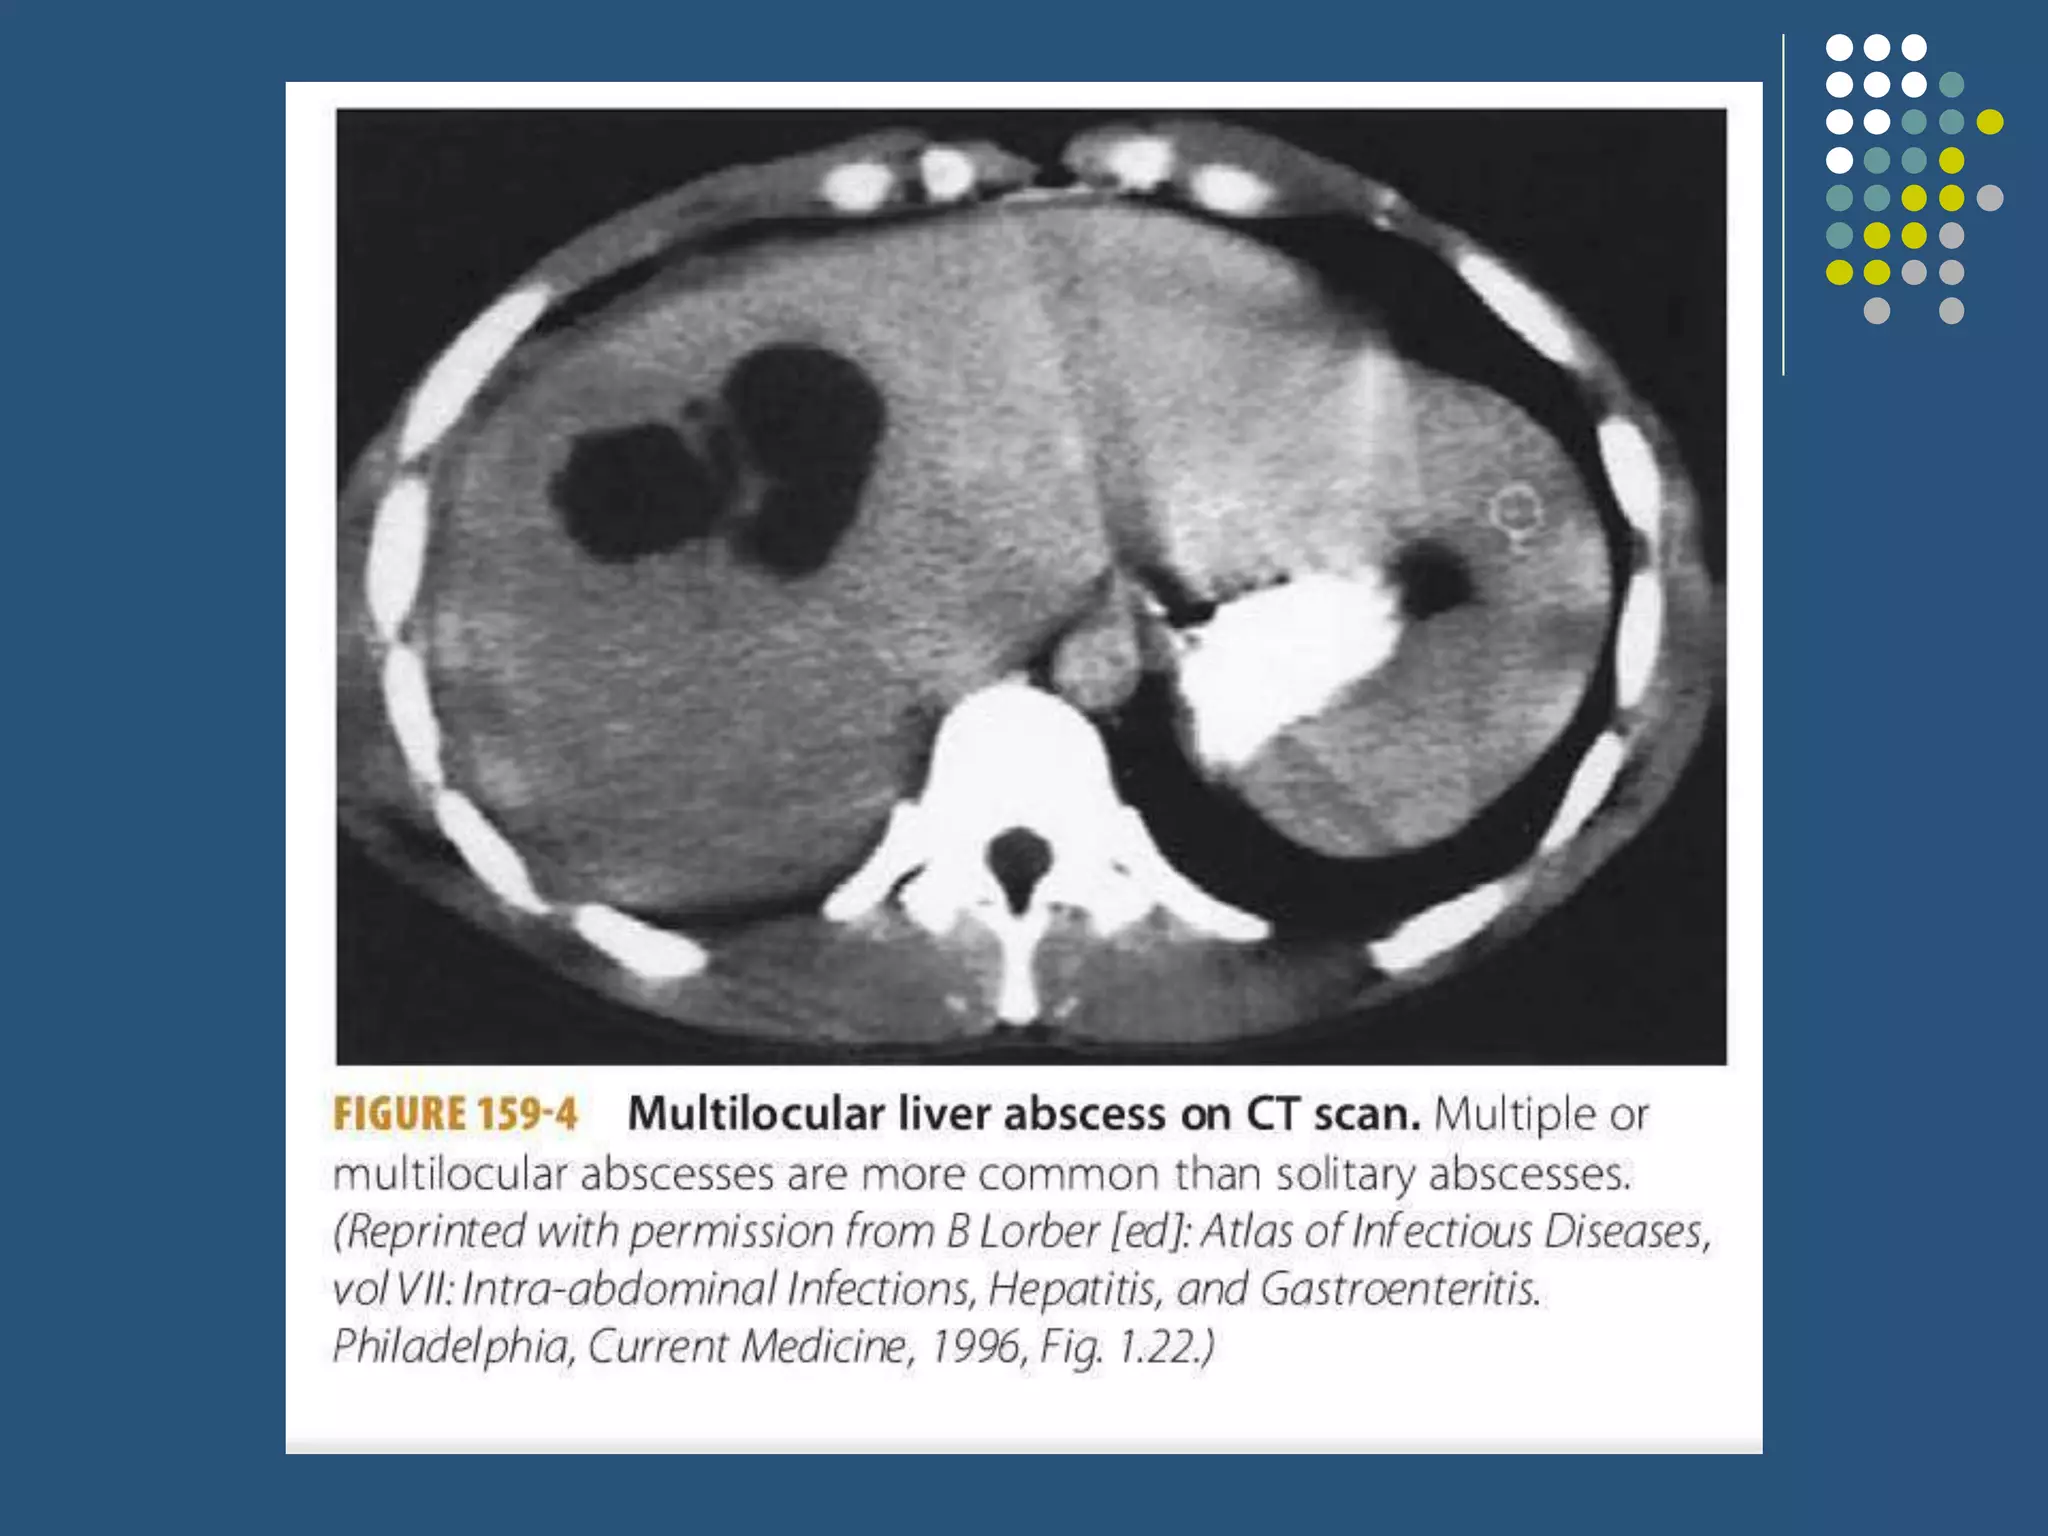

This case presentation describes a 60-year-old female patient who presented with 1 month of abdominal pain and 7 days of fever. Imaging revealed multiple rim-enhancing lesions in the liver consistent with pyogenic liver abscesses. The patient was diagnosed with pyogenic liver abscess and treated with intravenous antibiotics and drainage of the abscesses. Liver abscesses can have various causes but are often related to biliary tract or gastrointestinal infections. Diagnosis involves imaging and drainage or aspiration of pus is usually needed along with broad-spectrum intravenous antibiotics administered for at least 2 weeks.